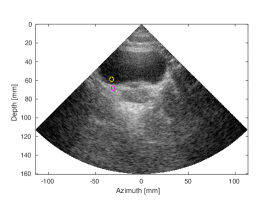

Results and discussion. Figure 3 and S- (in the supplementary material)

depict the SLT groundtruth, and the artifact-corrected and MLT images. Figure 3 demonstrates a number of anatomical structures in abdominal area, as depicted by the arrows. The CNN processing has restored the CR loss caused by the MLT cross-talk artifact for the MLT, and improved the CR by a dB for the MLT, as measured for aorta (yellow contour) and a background region (magenta contour). S demonstrates structures in a tissue mimicking phantom, such as anechoic cyst (the black circle marked by a yellow rectangle) and number of a point reflectors. Finally, S demonstrates a bladder (large dark cavity) and a prostate, located beneath it, scanned in a transversal plane. The output of our CNN was compared to the MLT image with Tukey () window apodization on receive, a common method to the attenuation of the receive cross-talk artifact.

| (a) SLT | (b) MLT, (Tukey, =0.5) | (c) MLT, CNN | |

| CNR=2.52, CR=-37.83dB | CNR=2.57, CR=-27.93dB | CNR=2.59, CR=-37.87dB | |